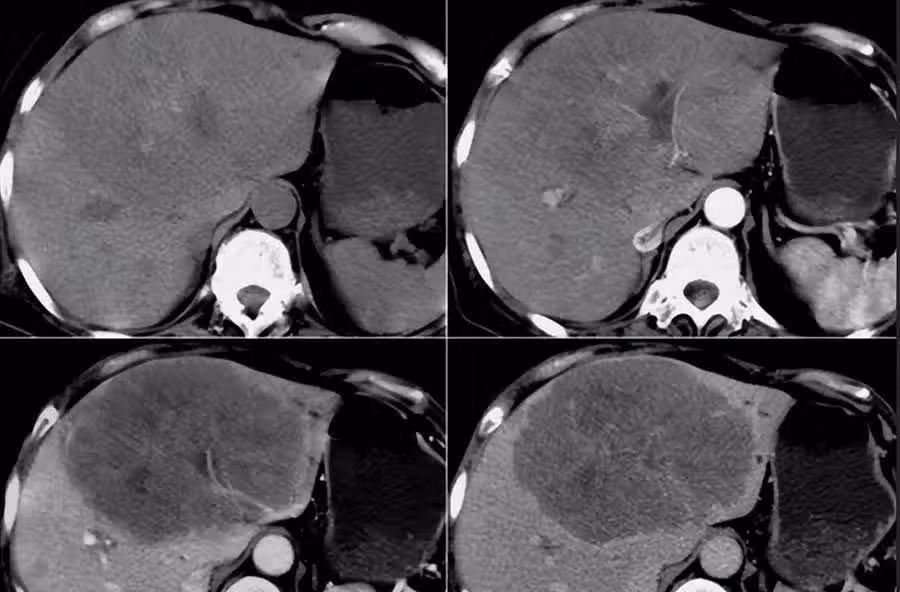

老王確診B肝14年不影響幹活, 但最近半個月老王總是出現上腹部疼痛且大便顏色呈棕黑色,去當地專科醫院做了血檢。 結果顯示他的轉氨酶高出正常兩倍多,CT結果顯示已經發展為肝癌晚期,且手術治癒率很低,讓老王和家人痛苦萬分。

據世界衛生組織統計我國肝癌發病占全球半數,死亡則占55%。那麼,今天我們來重點談一下怎麼才能在早期發現肝癌?什麼原因導致肝癌的發生?